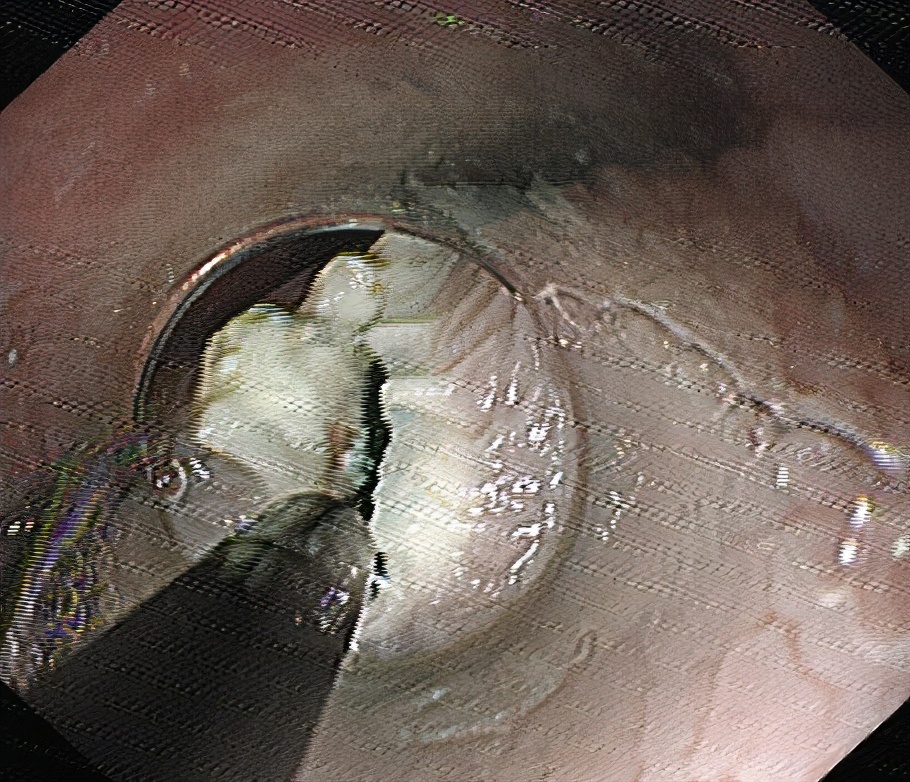

常规插入内镜,黏膜下注射。

食管粘膜层切开。

分离粘膜下层,建立黏膜下“隧道”。